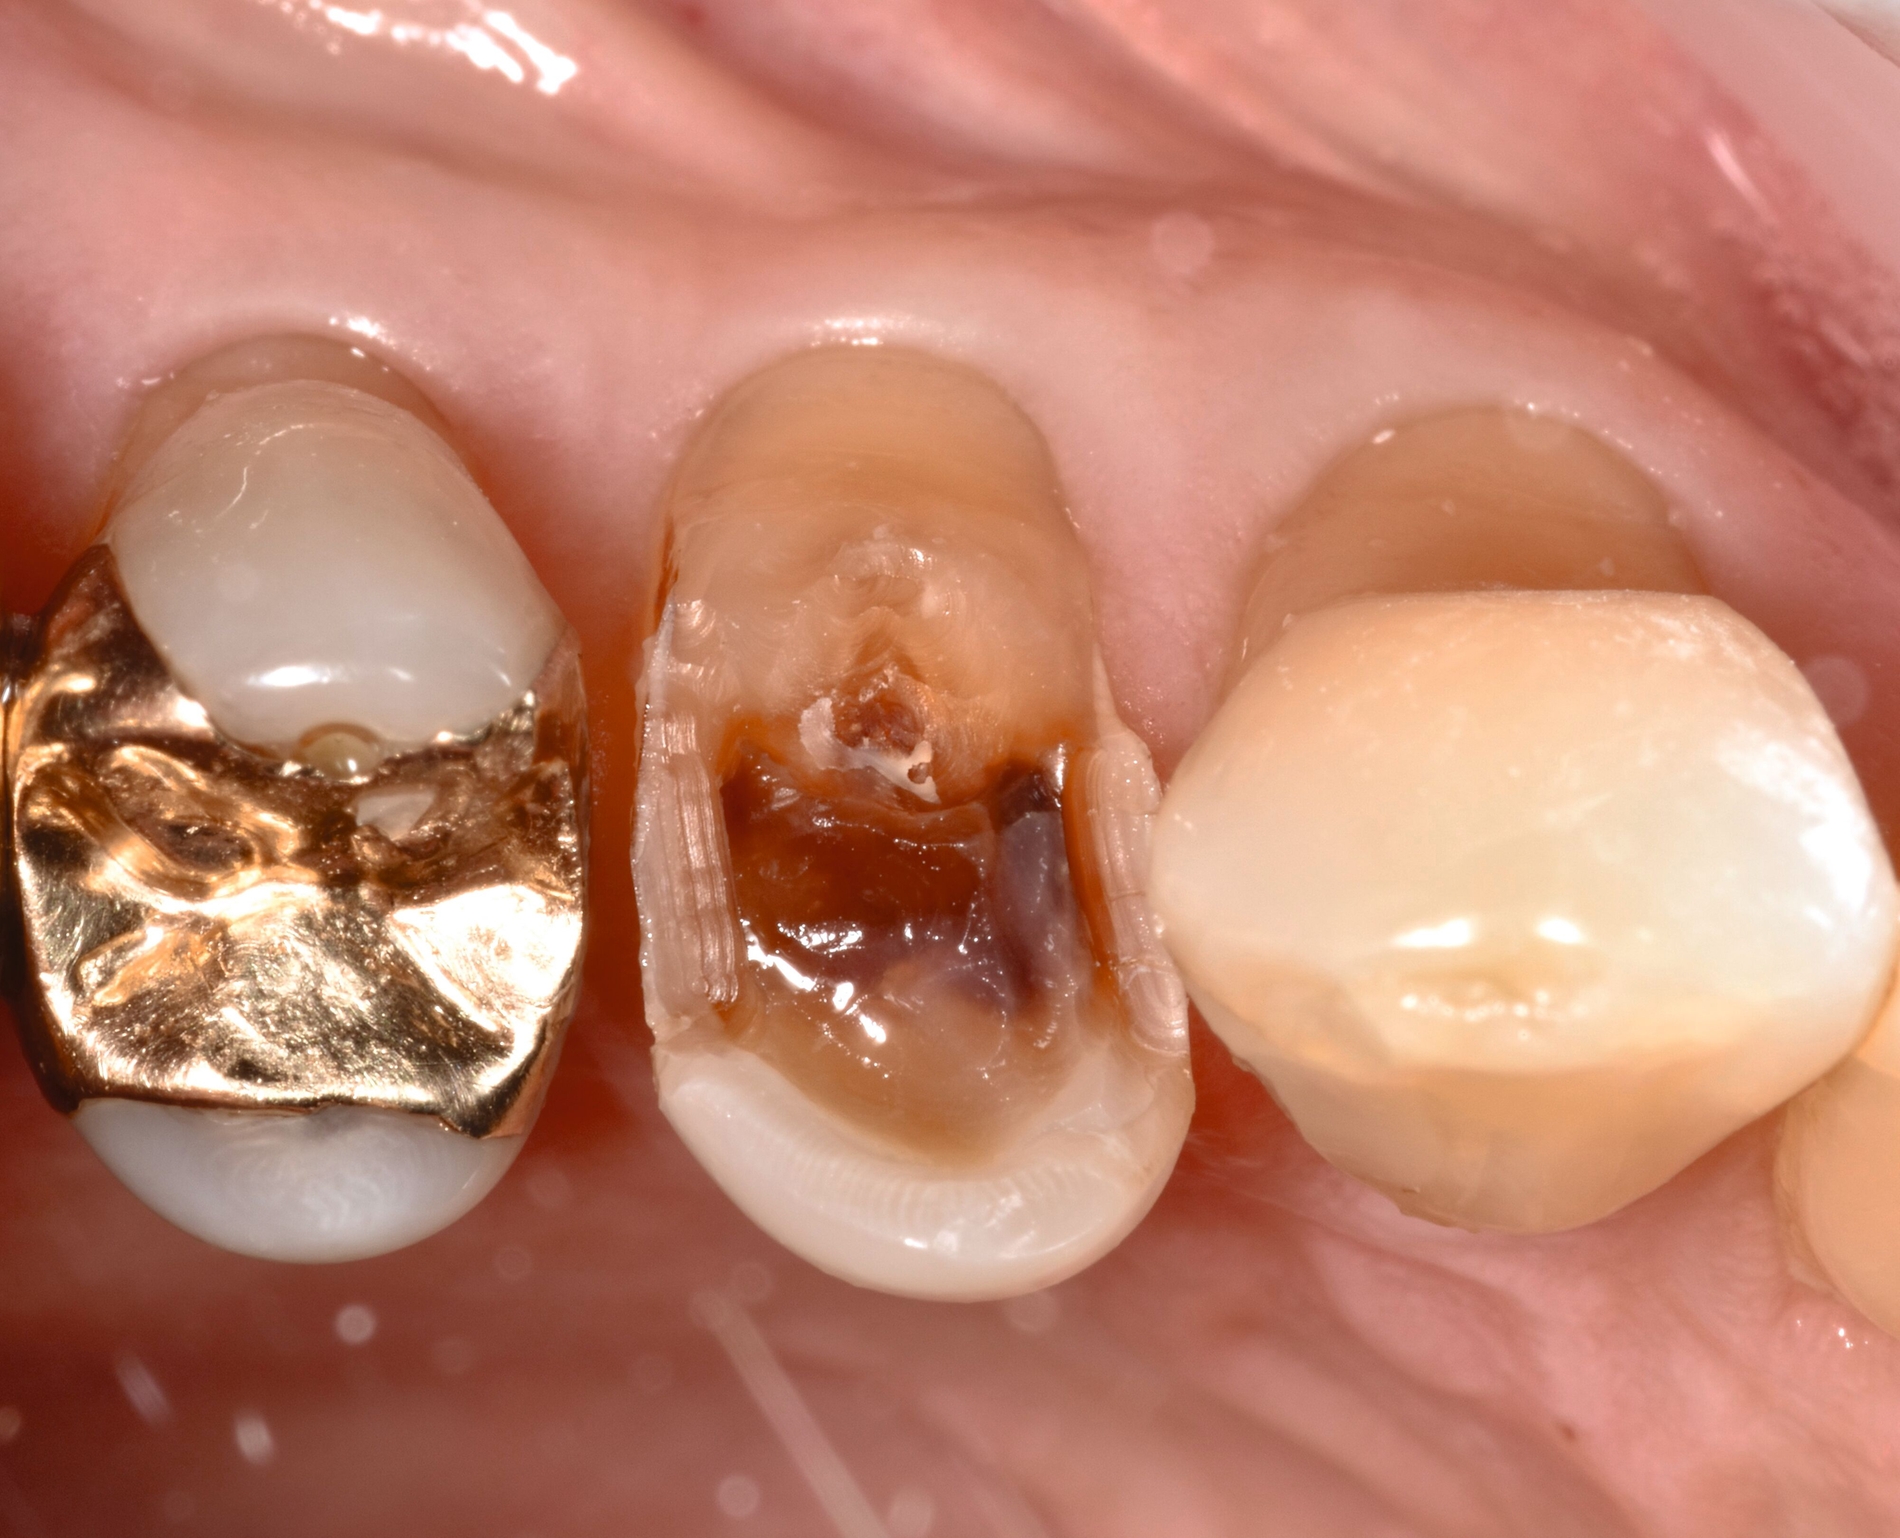

... mit Höckerersatz im Seitenzahnbereich

Für die Höckerüberkappung bedarf es eines ausreichend stabilen und abrasionsfesten Materials, das durch okklusale Kräfte belastet werden kann und die anatomische und funktionelle Rekonstruktion des Zahnes ermöglicht. Die Evidenz zur Verwendung von Kompositmaterialien bei Seitenzahnkavitäten mit Höckerersatz zeigt in mehreren Studien gute Überlebensraten [Deliperi et al., 2006; ElAziz et al., 2020; Fennis et al., 2014]. Van Nieuwenhuysen et al. [2003]berichtetenvon hohen Versagensraten sowohl bei Komposit- als auch bei Amalgamrestaurationen (30,4 Prozent beziehungsweise 28,1 Prozent). Diese Daten sind jedoch aufgrund der Verwendung älterer Kompositmaterialien als veraltet zu werten.

MERKE: Moderne Kompositmaterialien sind leistungsfähig und entsprechen den Prinzipien der minimalinvasiven Zahnmedizin. Insofern ist die Höckerrestauration mittels Komposit möglich (Abbildung 2).

Die Gruppe hat mit starkem Konsens die Empfehlung ausgesprochen, dass für Höcker-ersetzende Restaurationen insbesondere bei spezifischen Einflussfaktoren auf Zahn-, Mund- und Patientenebene (zum Beispiel eingeschränkte Compliance, schlechte Zugänglichkeit, komplexe funktionelle Rehabilitation) der Einsatz von indirekten Kompositrestaurationen erwogen werden kann.